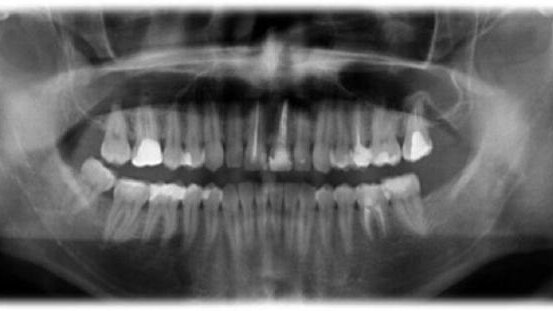

Autogenny przeszczep 3. trzonowców może stanowić doskonałą alternatywę dla odbudowy obszarów bezzębnych (Ryc. 1)1,2. Powszechnie twierdzi się, że leczenie kanałowe (RCT) autogennego przeszczepu zęba 36 powinno zostać przeprowadzone w czasie 14 dni przed rozpoczęciem poważnych reakcji zapalnych.7,8 W niniejszym opisie przypadku pacjent zgłosił się ponownie 6 miesięcy po zabiegu chirurgicznym z objawami zapalenia tkanek okołowierzchołkowych (AP) związanymi z przeszczepionym zębem (Ryc.2).

Pacjent zgłosił się ponownie dopiero po 6 miesiącach z objawami dyskomfortu podczas żucia, tkliwości opukowej, przejściowej opuchlizny oraz negatywnej reakcji na testy termiczne. Przeprowadzone badania radiograficzne potwierdziły wstępną diagnozę AP (Ryc. 2).

Jak potwierdza niniejszy opis przypadku, 6 miesięcy po przeszczepie widoczna była poważna reakcja zapalna – czas ten przekraczał wszystkie zalecenia dotyczące okresu na przeprowadzenie RCT.4 Może to również podkreślać znaczenie przestrzegania przez pacjenta ustalonego wcześniej protokołu.6